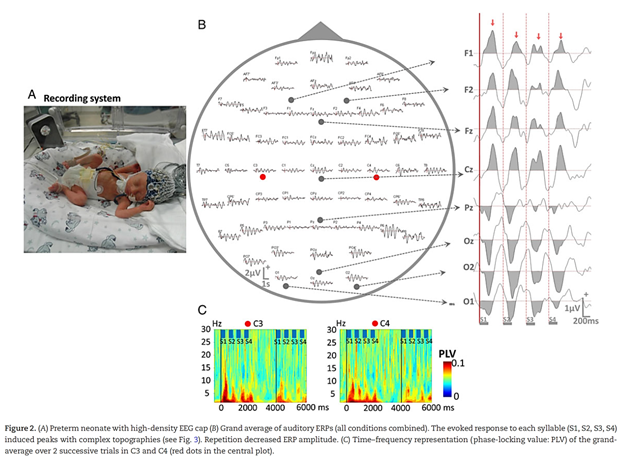

Modern studies often adopt a multimodal strategy, combining structural imaging with functional measures, to chart how neural circuits evolve over time. For instance, neuroimaging in very early preterm infants reveals how auditory cortex responses mature in both time and frequency domains, offering early biomarkers of neurodevelopmental risk.